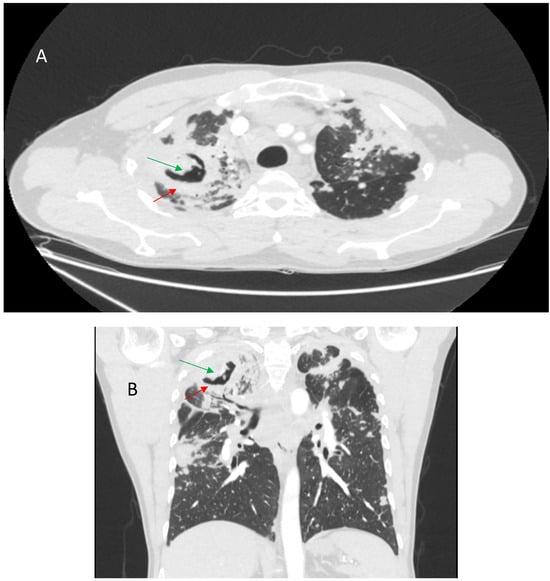

9.1. Infections

9.2. Pulmonary Hypertension and Pulmonary Embolism